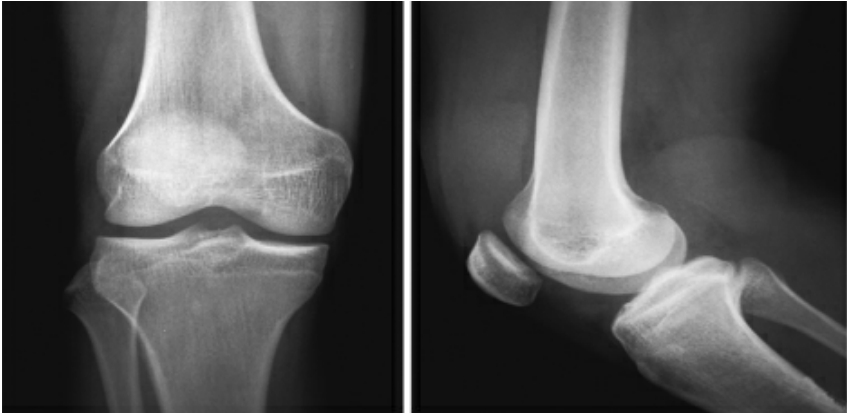

正常膝关节X片